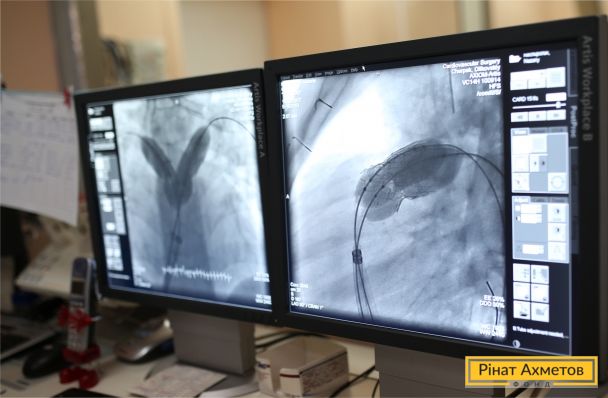

Стишок от 2-летней Элечки для доктора Андрея Максимекно, который спас ее маленькое сердечко.

Элина одна из 35 детей, которые получили помощь от Гуманитарного штаба в рамках проекта «Здоровое сердце». О том, кто и как поможет получить помощь, читайте на сайте: https://www.fdu.org.ua/get_help